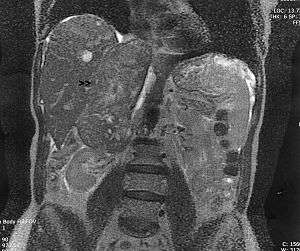

Leiomyosarcoma of the adrenal vein. Coronal view of abdominal MRI. Tumor (arrow) extends from the superior pole of the right kidney to the right atrium. | |